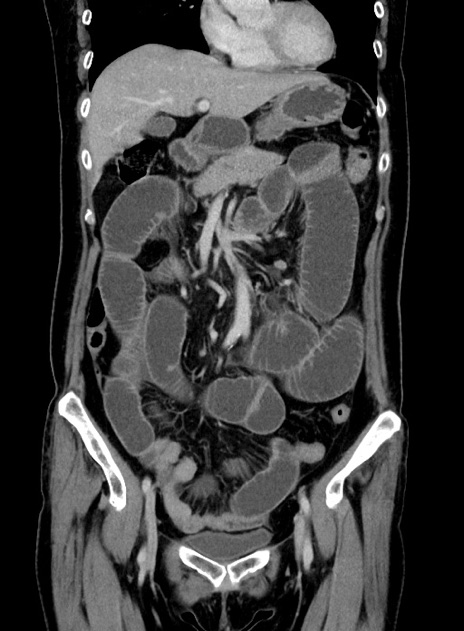

症例9(冠状断像)

【症例】 60歳代女性

【主訴】むかつき、みぞおちの痛み

【現病歴】3日前よりむかつきがあり、食事がとれない。

【既往歴】糖尿病

【身体所見】発熱なし、心窩部圧痛軽度あるも、腹膜刺激症状なし。

【データ】WBC 7400、CRP 1.92